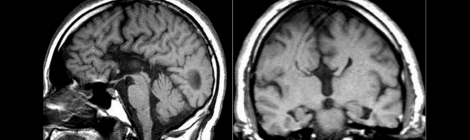

Development of the Corpus Callosum & Its Relationship to Autism

For those who are unfamiliar, the corpus callosum is a large bundle of communicative fibers that connects the two cerebral hemispheres, allowing crosstalk between them. Below are some DTI images […]